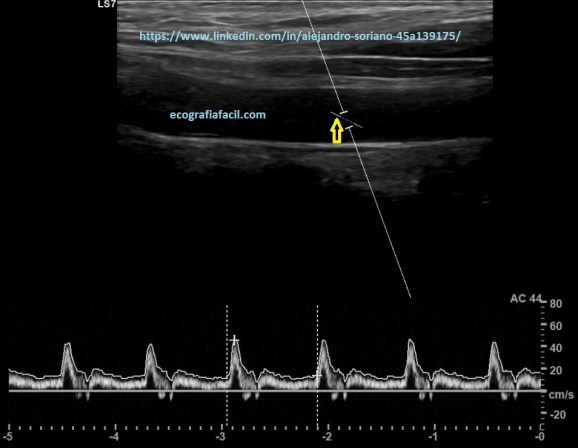

Como vemos en las tres imágenes con distintas angulaciones obtendremos un espectro bastante decente pero no en todos los casos obtendremos datos suficientemente fiables.

En la imagen 11 hemos conseguido poner la línea paralela pero a cambio de una angulación superior a 60º; por tanto, tendremos que “jugar” con la angulación del vaso y la del propio Doppler para tener un ángulo inferior a 60º y que quede la línea paralela a la pared del vaso como tenemos en la imagen 12. Esto nos permitirá tener la tranquilidad de que los datos obtenidos serán más fiables.